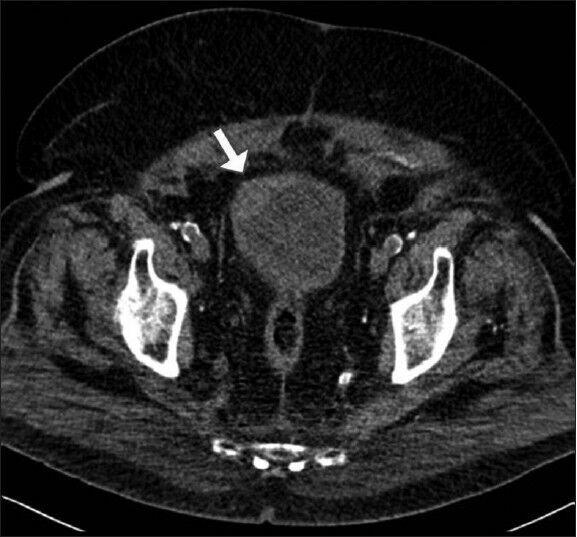

Radiation-related osteosarcomas are well described malignant mesenchymal neoplasms, yet their pathogenesis is not fully understood. They are generally classified into either skeletal osteosarcomas, or their and rare soft tissue counterpart. The occurrence of osteosarcoma in the urinary bladder (UB) following radiotherapy is exceedingly rare. To the best of our knowledge, only two cases of radiation-related urinary bladder osteosarcoma have been published; we herein describe another case of an 85-year-old man who developed post radiotherapy chondroblastic osteosarcoma of the urinary bladder four years following initial surgical resection and radiotherapy for bladder urothelial carcinoma. We believe that this is the first case of radiation-related chondroblastic osteosarcoma arising in the urinary bladder. In addition, we review the literature and explore the possible histogenesis of this rare neoplasm.